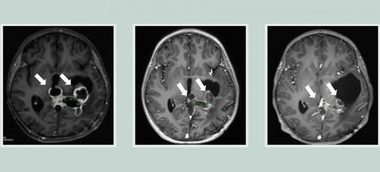

La doi ani şi opt luni după ce a fost singurul participant la studiul clinic, Trotman, acum în vârstă de 43 de ani, nu mai are tumoarea, iar investigaţiile imagistice au indicat că estre sănătos.

„Este foarte neobişnuit să avem o scanare complet curată în cazul unui glioblastom, mai ales în condiţiile în care el nu a mai făcut operaţia de îndepărtare a întregii tumori, aşa cum fusese planificat iniţial”, a explicat dr. Mulholland. „Sperăm că imunoterapia şi tratamentele ulterioare pe care Ben le-a urmat vor ţine tumora sub control – şi până acum aşa a fost, ceea ce ne bucură enorm”, a adăugat medicul.